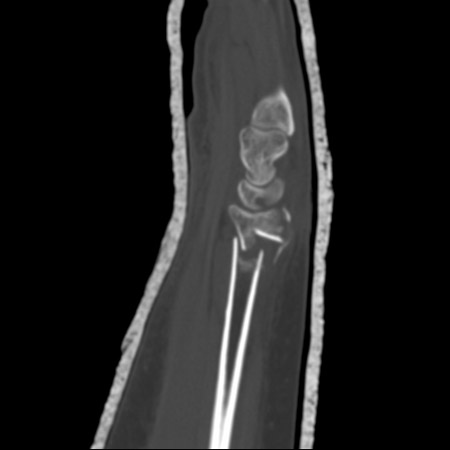

As tomografias computadorizadas (TCs) do punho fornecem detalhes excelentes para avaliação da geometria da fratura, do comprometimento articular e do grau de cominuição

Do acervo do Dr. Chaitanya S. Mudgal